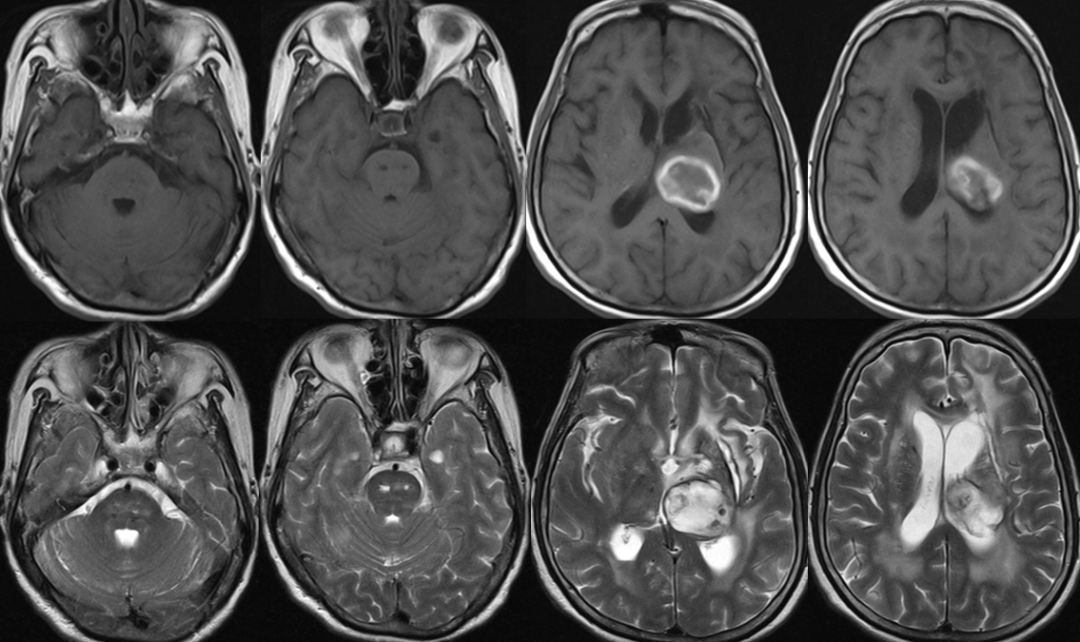

2014-11-27 MRI

渗透性脱髓鞘综合征?

渗透性脱髓鞘综合征(osmotic demyelination syndrome,ODS)

是一种少见的急性非炎性中枢脱髓鞘性疾病,主要是由于慢性低钠血症时脑细胞已经适应了一种低渗状态,此时一旦给予迅速补钠,血浆渗透压迅速升高造成脑组织脱水而继发脱髓鞘。

分为脑桥中央髓鞘溶解症(central pontine myelinolysis, CPM),脑桥外髓鞘溶解症(extrapontine myelinolysis, EPM)。

CPM表现为四肢瘫和不同程度的脑干功能障碍,如假性延髓麻痹,偶有闭锁综合征、缄默症。EPM主要表现为运动障碍、肌张力障碍、帕金森综合征等,仅出现小脑体征者罕见。

影像学特征

CT表现为脑桥中央或脑桥外病灶处的低密度影。

MRI能更好地反映病灶的数量和程度。早期可无异常,出现症状后1周DWI上可发现高信号。急性期表现为对称的T1WI低信号,亚急性期可能是由于内皮细胞受损所致的微出血而显示T2WI高信号。FLAIR显示病灶高信号更清楚,能更好地显示临近脑脊液的病灶,比如大脑皮质,应作为常规检查。也有一些报道发现皮质层及皮质下T1高信号,有的钆增强被强化,有的不被强化。脑MRI对本病具有十分重要的诊断意义,大约在发病2~3周时异常信号最为明显,所以结合病史及临床表现如果考虑ODS的诊断,在MRI检查正常的情况下,在出现症状后10~14天复查MRI是十分重要和必要的。